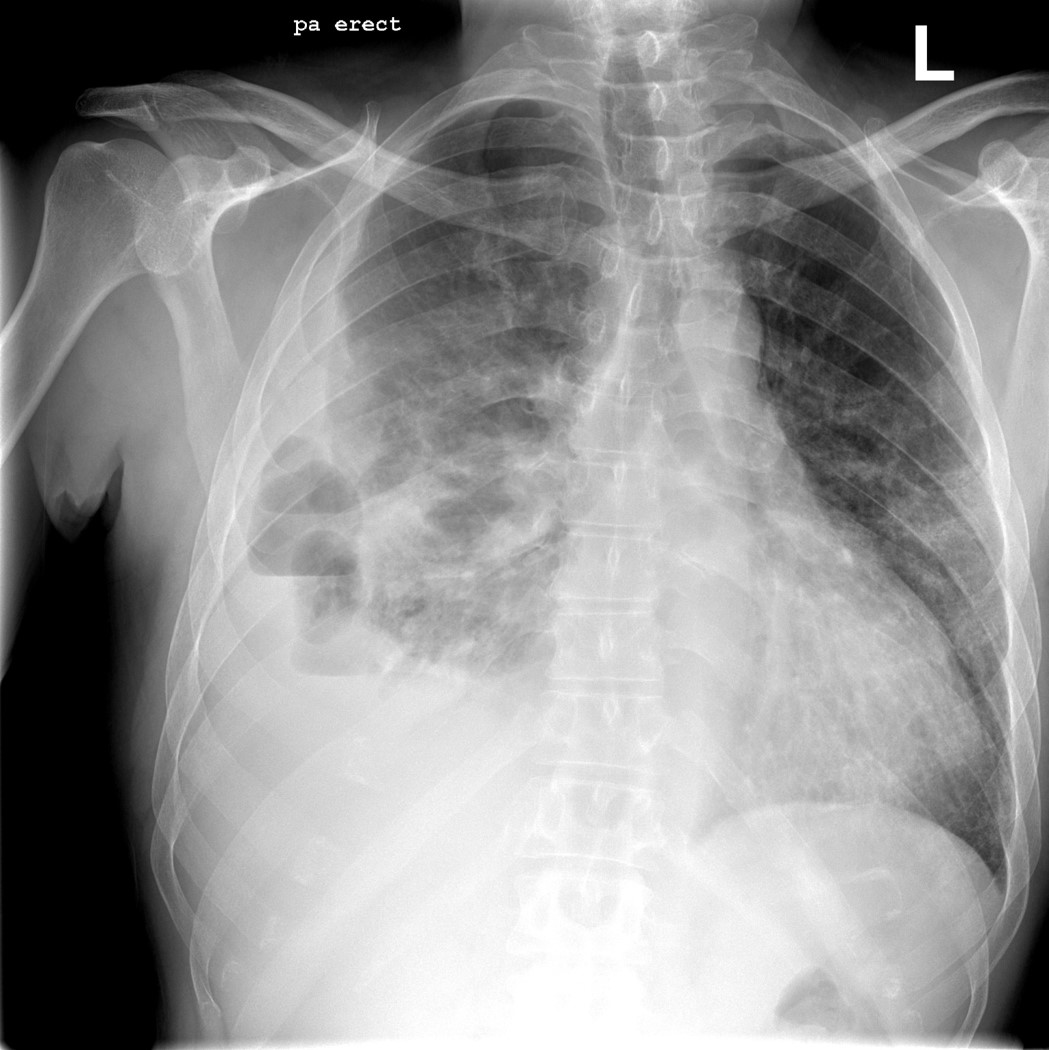

Case Report: 51 year old man with worsening pneumonia while hospitalized

Christopher Cirino, DO, MPH